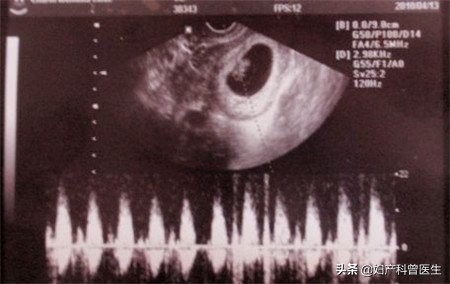

第一次:停经约6-8周

大概是停经50天左右,检查孕囊的情况(宝宝居住的"房子"),查看胚芽大小可推测孕周,如有胎心管搏动,就表示小生命有心跳了。早孕超声还有一个重要的目的就是确定是否为宫内妊娠,排除宫外孕及葡萄胎,查看单胎还是多胎。